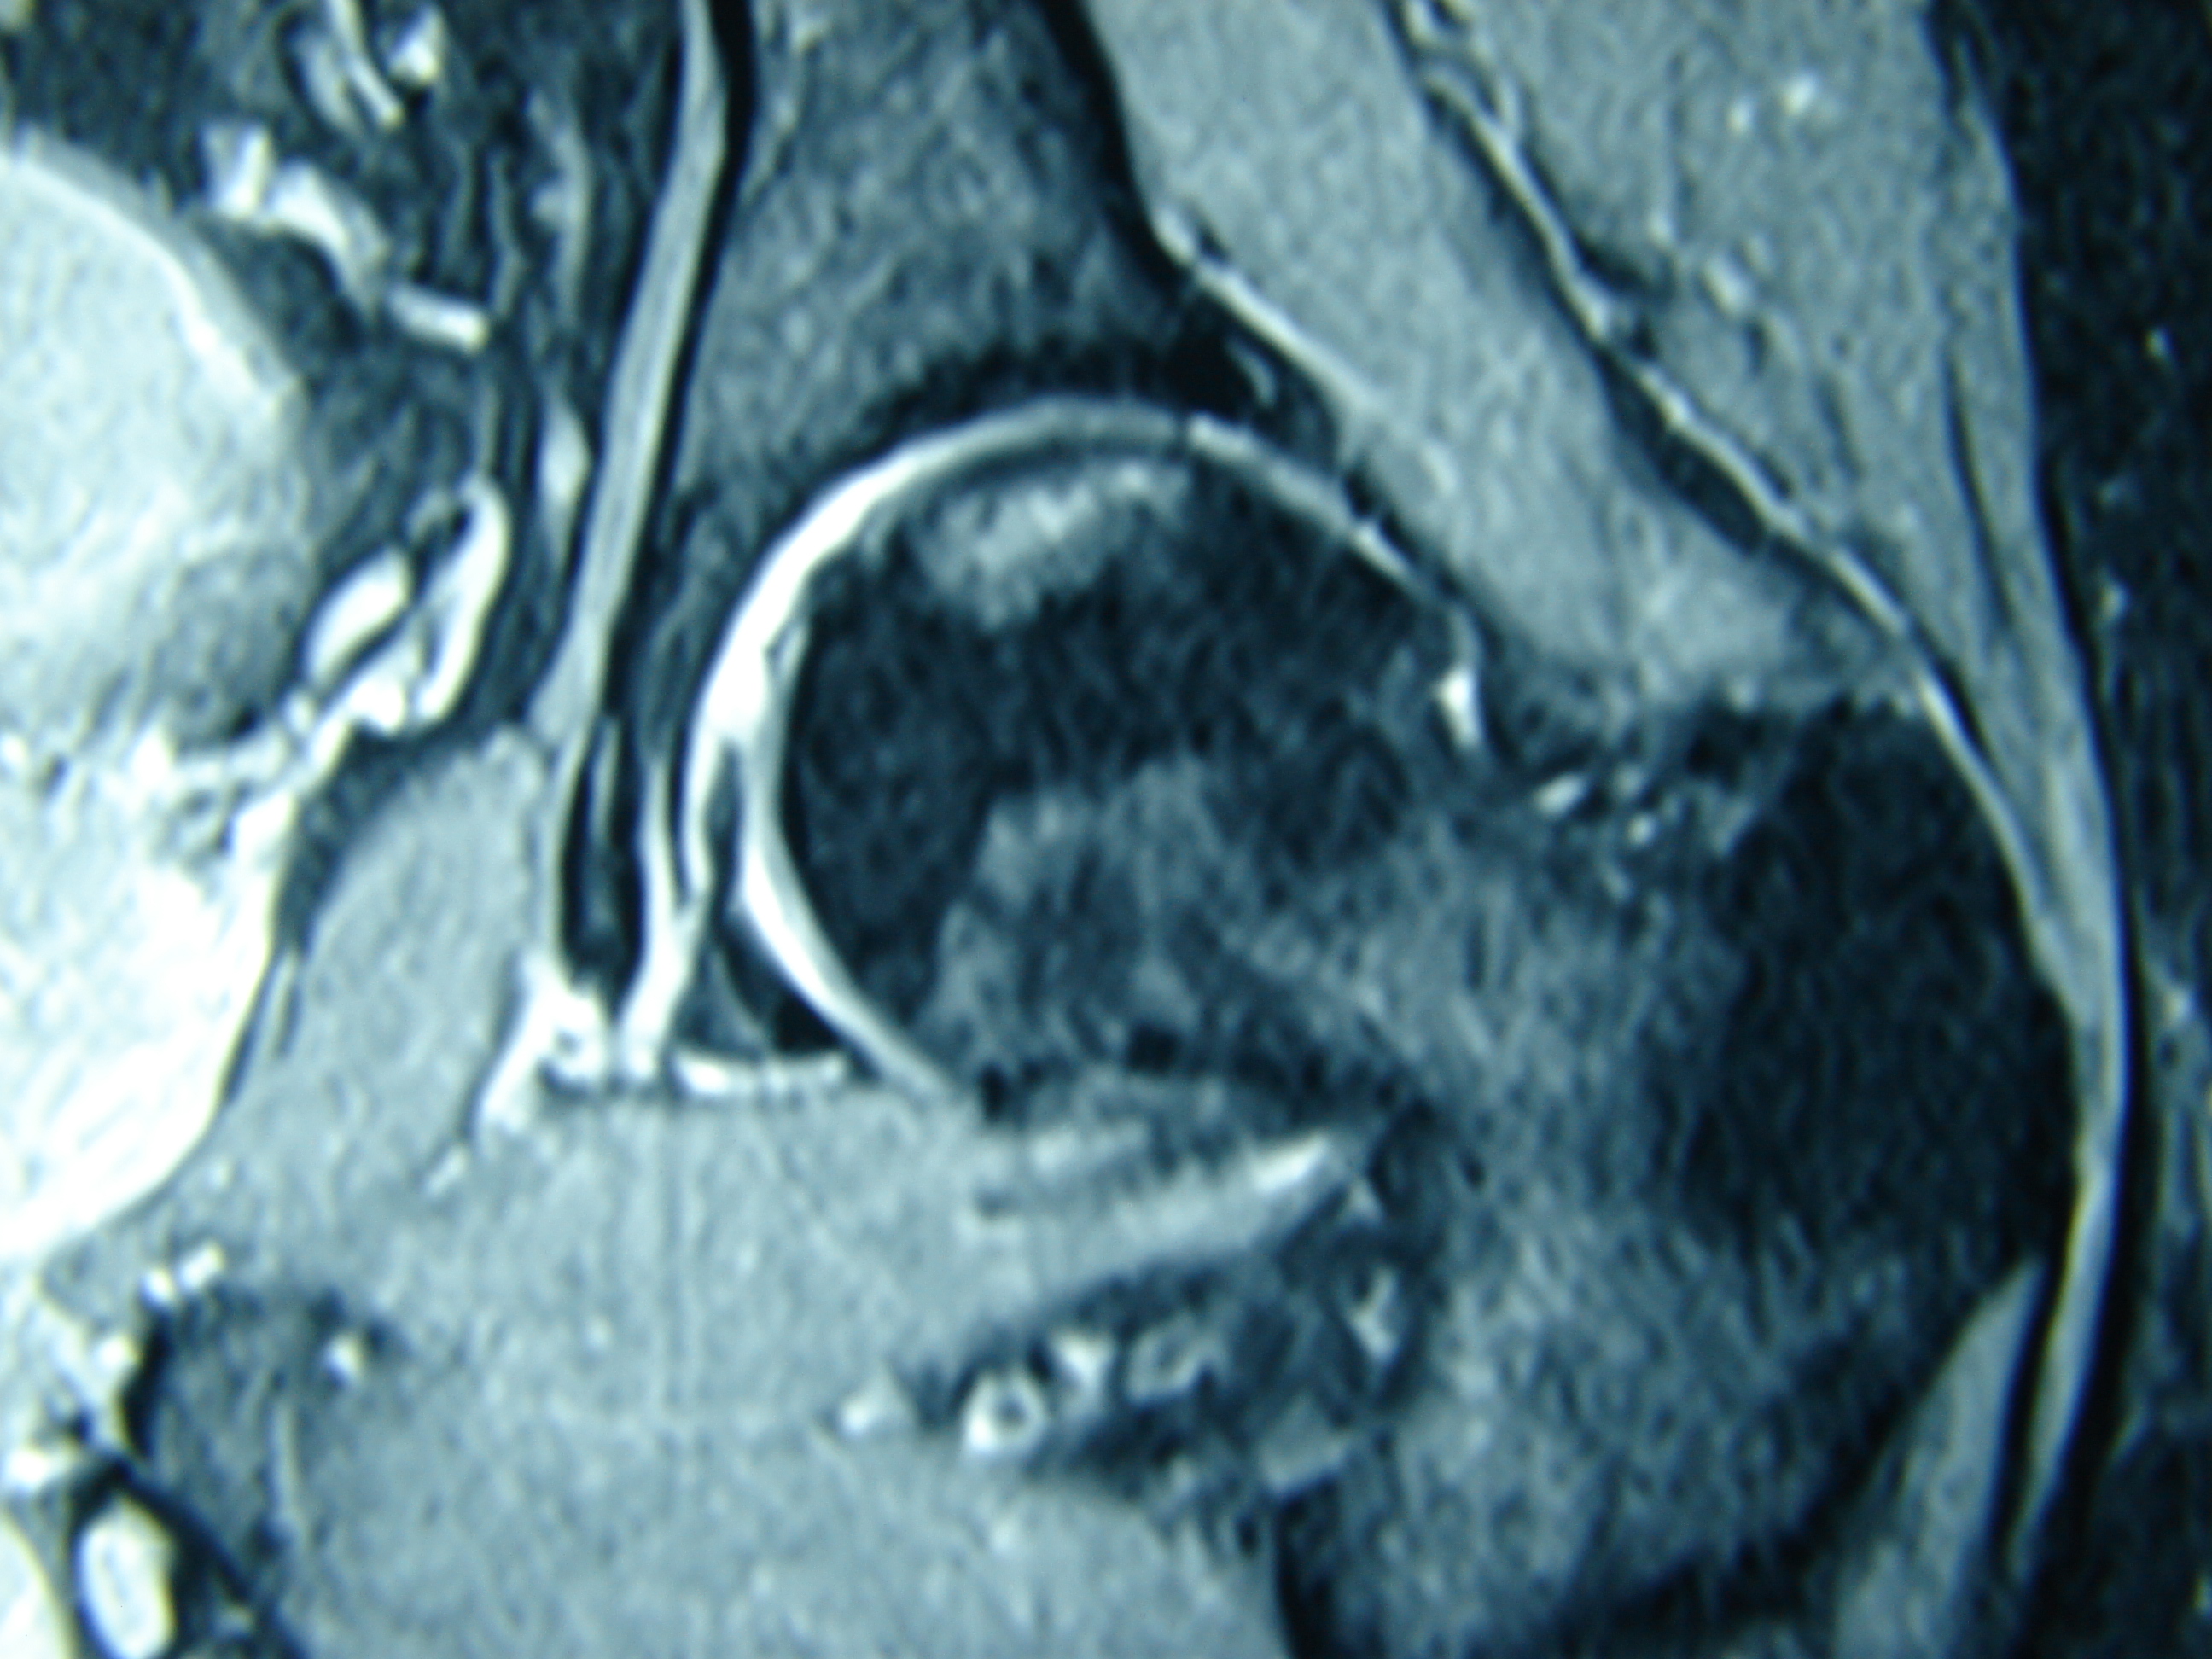

Εικόνα 2: Μαγνητικη τομογραφία των κατ’ ισχίων αρθρώσεων

Είναι εμφανής η οστική βλάβη της μοιριαίας κεφαλής η οποία δε συνοδεύετε από καθίζιση της αρθρικής επιφανείας.